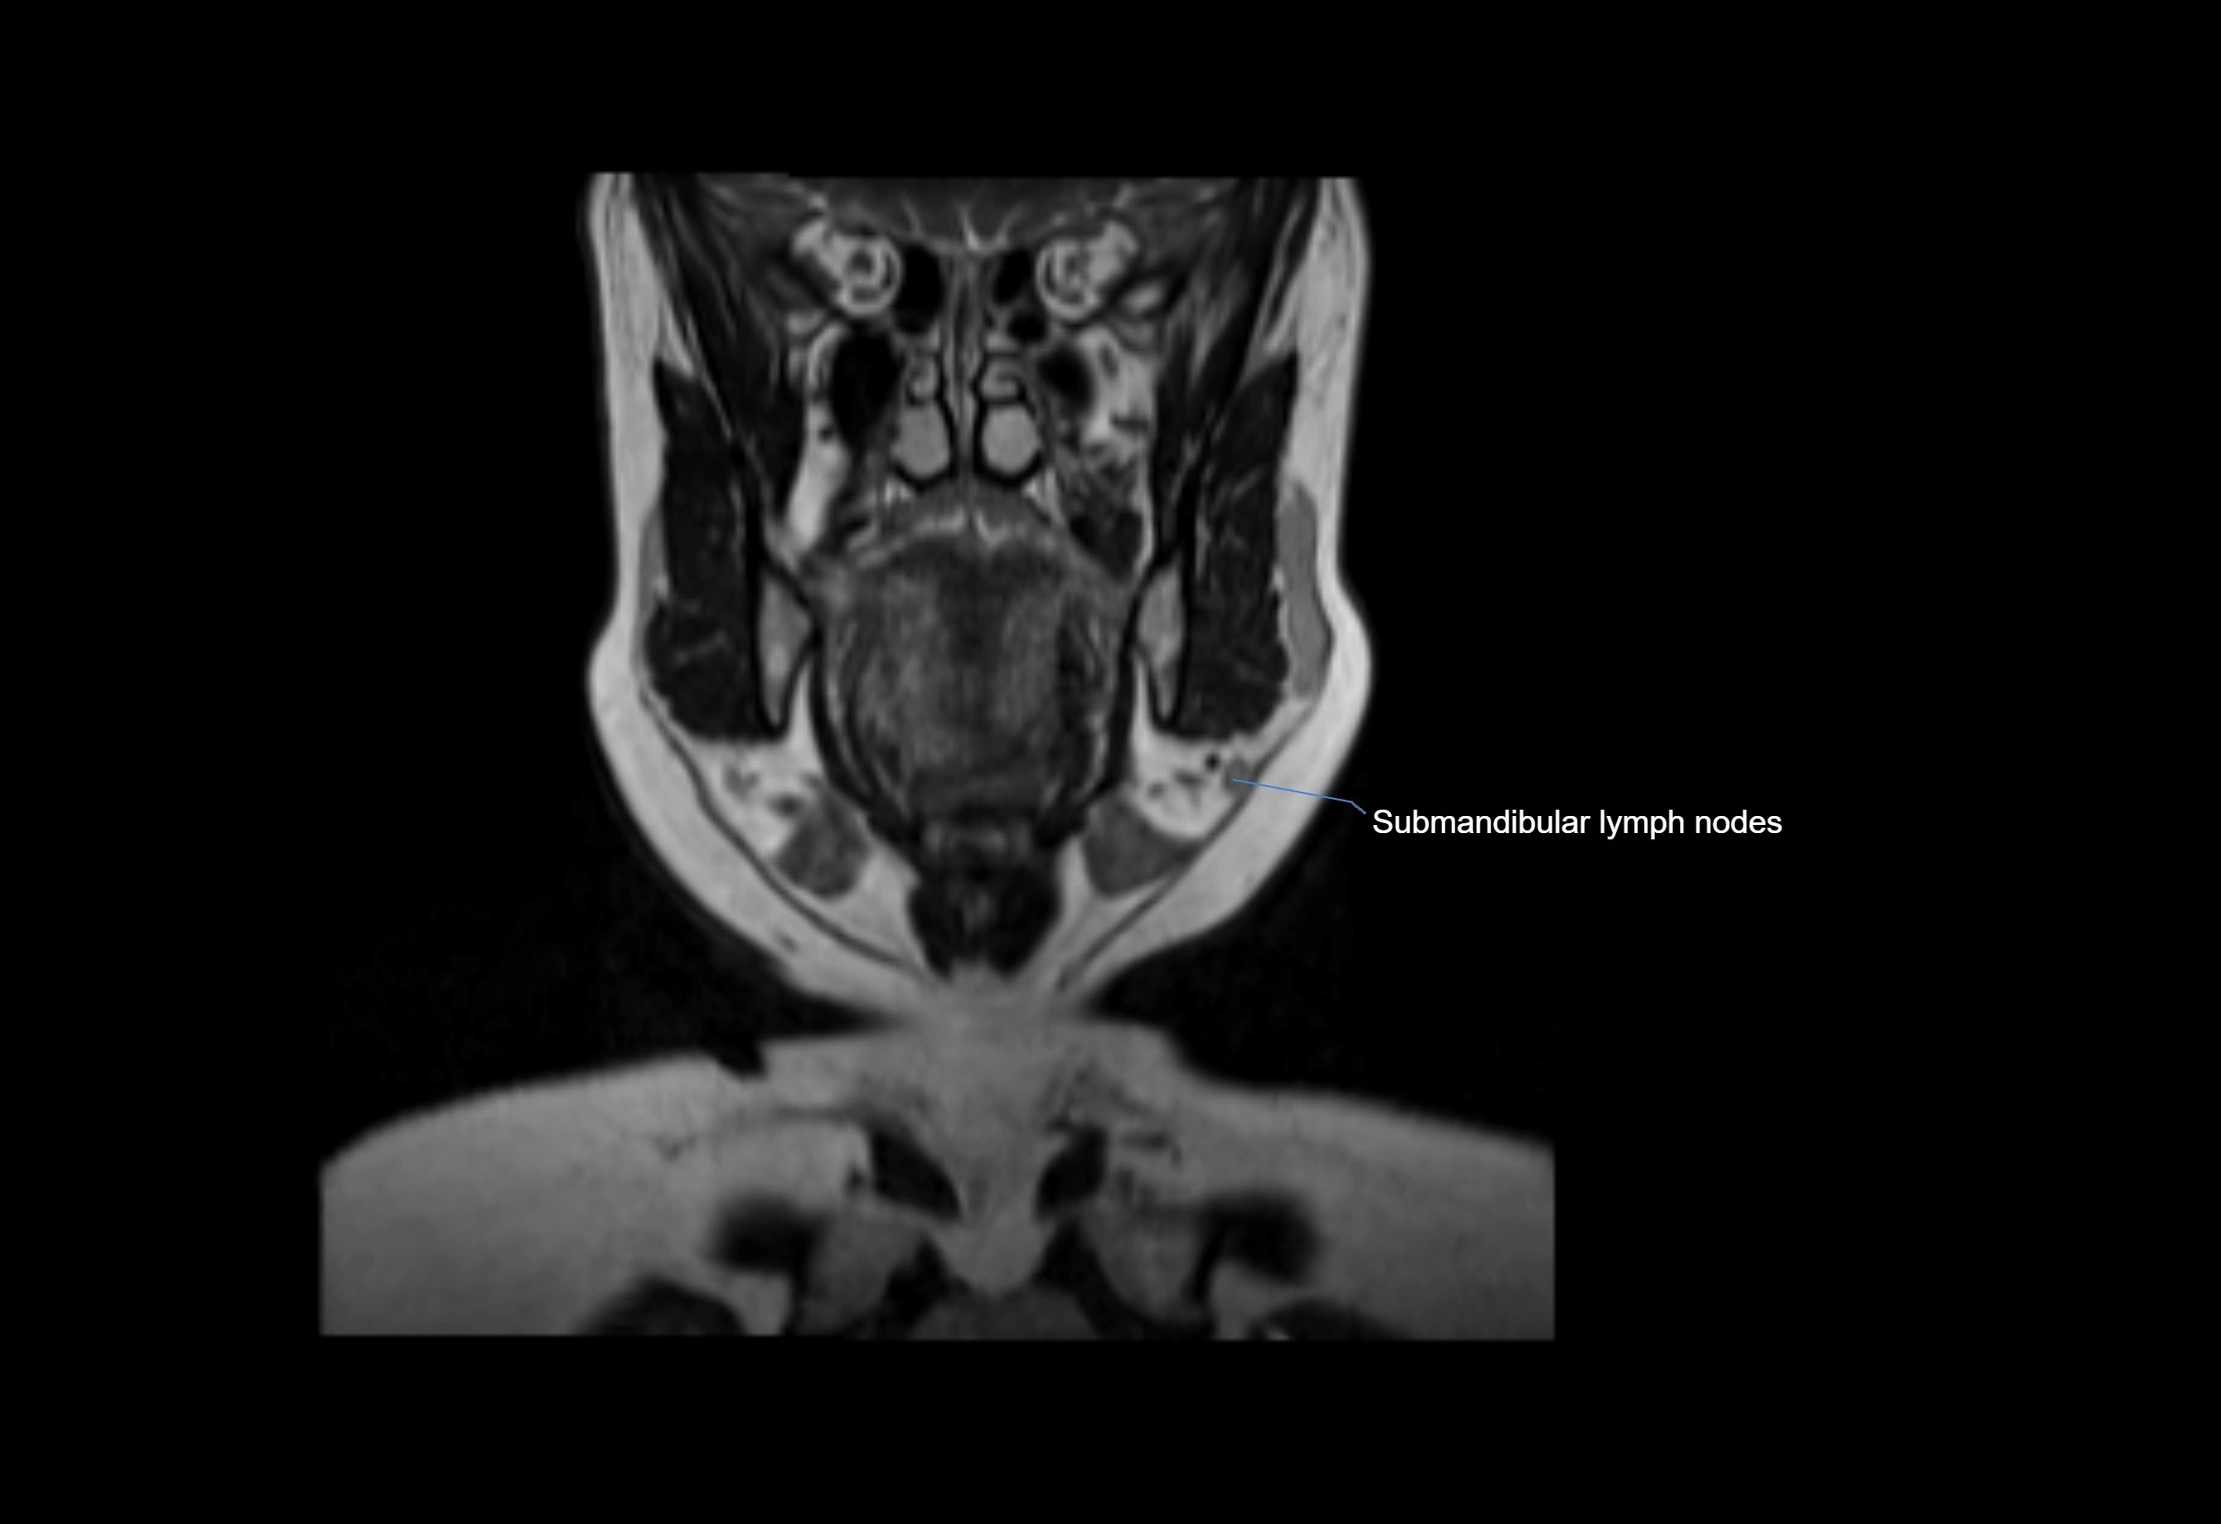

MRI images

image